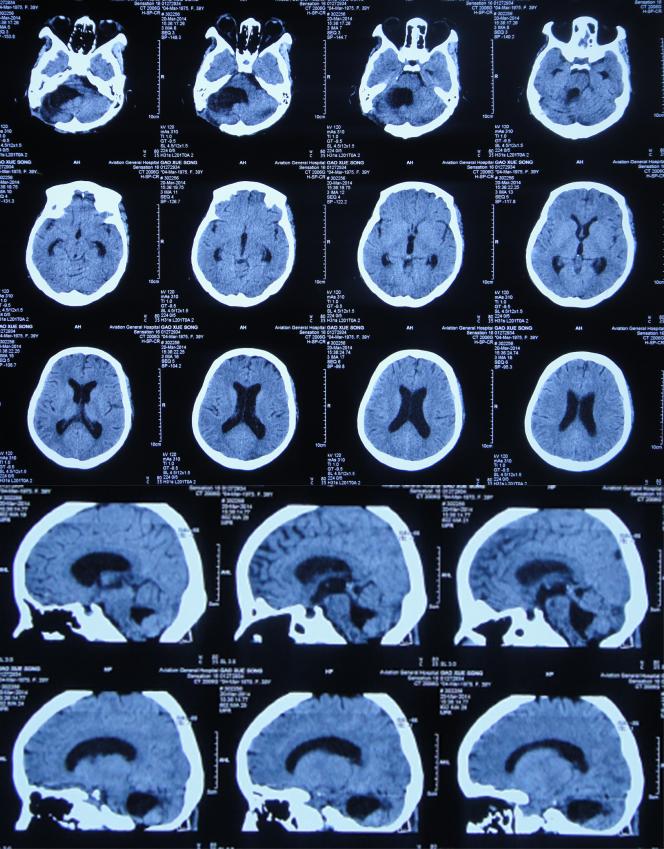

患者高老师是一名高中历史教师,右耳听力减退已10余年未给予特殊治疗,但2013年11月因出现病情严重的头疼头晕症状,到当地的山西省静乐县某医院,查头颅CT(图-1)后颅内肿瘤占位,需要手术。

图-1:2013年11月6日头颅CT